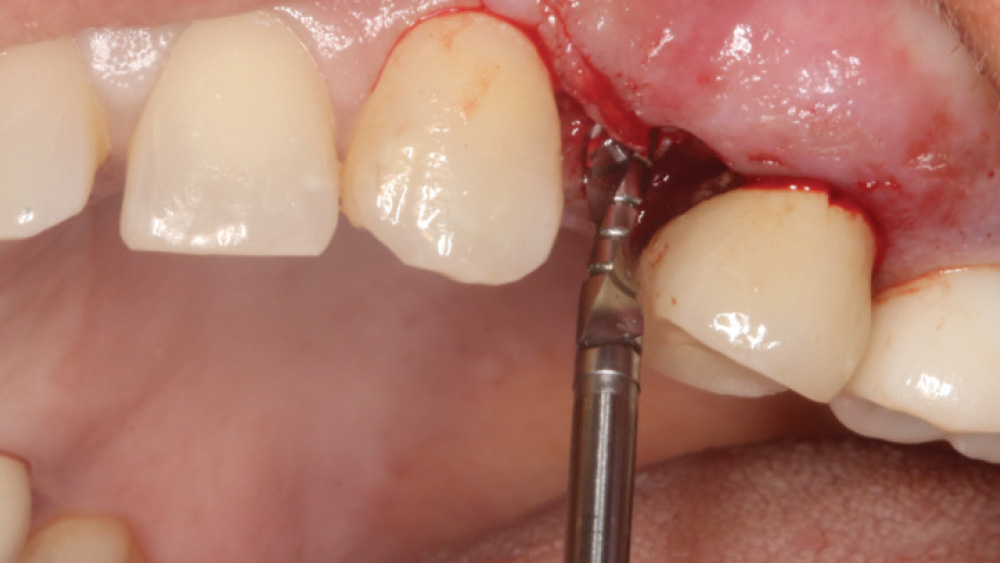

In contrast, with a flapless procedure, a tissue punch is used to gain access to the bone through the gingiva, minimizing postoperative discomfort by eliminating incisions in the mucosal tissue. Whenever mucosal tissue is incised, prostaglandin and histamine are released, resulting in potential postoperative swelling and pain. Therefore, when there is an adequate width of attached gingiva on the facial aspect of an implant site, a flapless procedure may be indicated, eliminating any suturing requirements.

CASE REPORT

The following case, which I performed alongside Dr. Stephanie Tilley of Pensacola, Florida, illustrates the use of both surgical techniques for the same patient, who presented with edentulous spaces in the areas of both right and left maxillary first bicuspids. Due to varying soft-tissue volume on each side of the arch, implant surgery was performed using a flapless procedure for one site, while the attached gingiva was reflected to expose the available hard tissue for the other. As a result of proper site evaluation, treatment planning and restorative-driven implant placement, both surgical techniques led to successful outcomes for the patient.